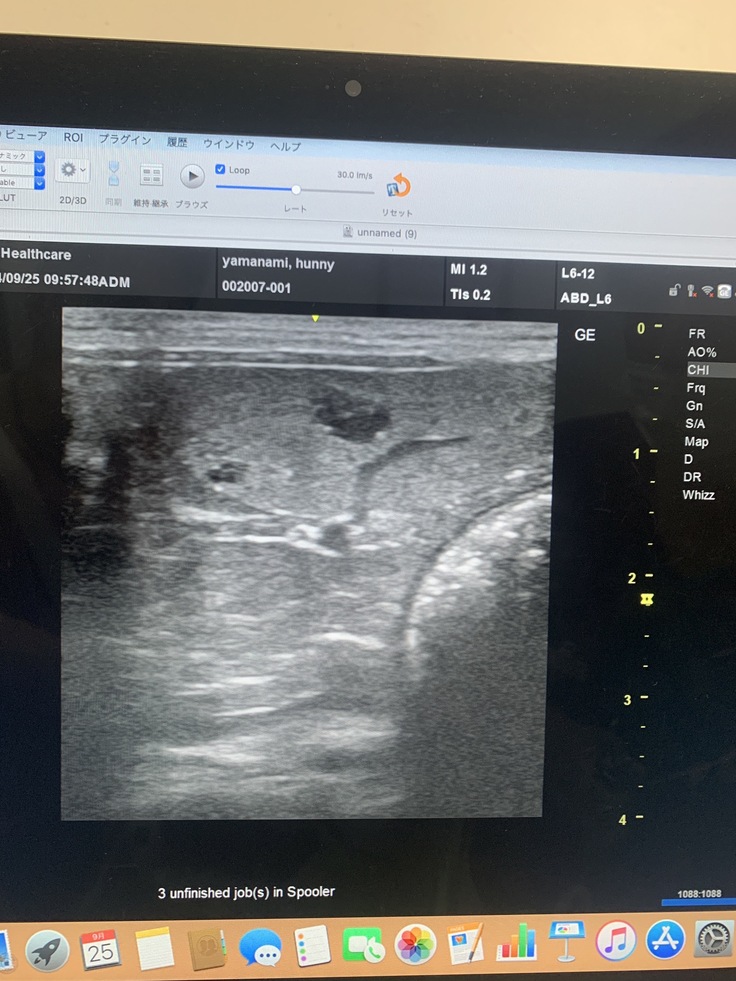

脾臓にしこり、影→1センチ4ヶ所が見つかった

おそらく、脾臓の腫瘍も転移したものの可能性が高い…

放射線がきいてくれた!扁桃腺とリンパ節の腫瘍が小さくなった!!と思ったら骨転移…そして腹膜炎に、腹水、更には脾臓転移…